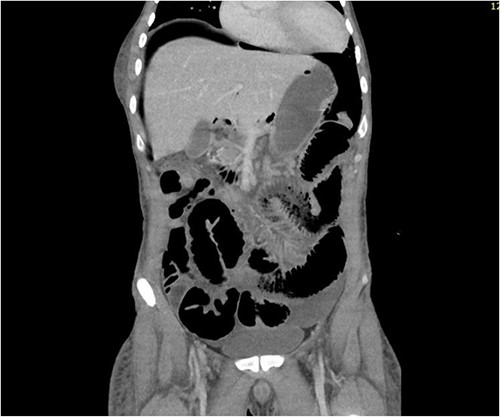

CT abdomen revealed a large amount of free air throughout the abdomen, mostly localized anterior, but also perihepatic, perigastric, paracolic, and perisplenic (Figs 1 and 2).

CT abdomen showing a large amount of free air mostly localized anterior.

CT abdomen showing large amount of free air throughout the abdomen.